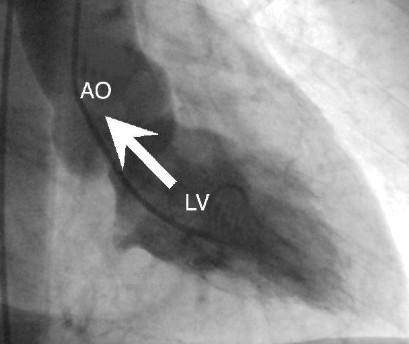

Figura 5. Sem regurgitação mitral

AO: aorta. LV: ventrículo esquerdo